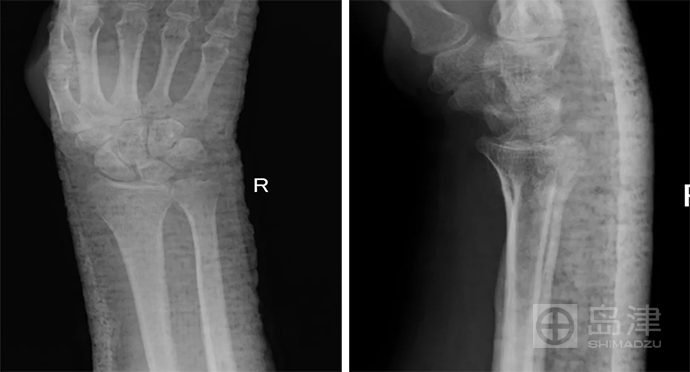

病例四:异物成像

女性, 50岁 ,右桡骨远端骨折后石膏固定,要观察骨折对位对线情况。无法拆除石膏,X线平片上高密度的石膏遮掩了骨折征象的显示。

DTS 检查避免了异物遮掩的影响,可以清晰观察骨折线及愈合情况。

异物干扰,DR无法显示

DTS骨折线清晰可见

图像来源:西安市第九医院